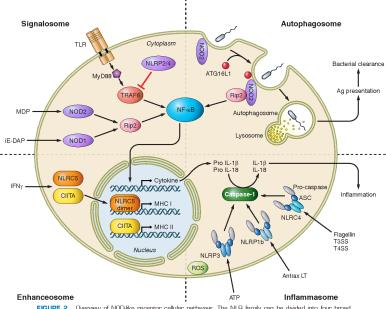

TLR2 Antibodies Background

Research Area for TLR2

- Cancer Cancer and Inflammation Intracellular Factors in Inflammation

- Cancer Cancer and Inflammation Ion Channels and Regulators

- Cancer Cancer and Inflammation Neuroinflammation

- Cancer Cancer and Inflammation Pattern Recognition Receptors

- Cancer Cancer and Inflammation Platelets

- Cancer Cancer Biomarkers Gastric Cancer Biomarkers

- Cardiovascular Atherosclerosis Ion Channels and Regulators

- Cardiovascular Atherosclerosis Platelets

- Cardiovascular Vascular Endothelium GTPases and Regulators in Endothelial Cells

- Developmental Biology Immune System Development Hematopoiesis

- Immunology Immunocyte Markers Macrophage (M1,M2)

- Immunology Innate and Adaptive Immunity Toll-like Receptors

- Immunology Receptors of the Innate Immune System Receptors of The Innate Immune System

- Immunology The Hemopoietic System Platelets

- Neuroscience Neurodegenerative Diseases Neuroinflammation

Signaling Pathway for TLR2

Cell Signaling

Cell Signaling